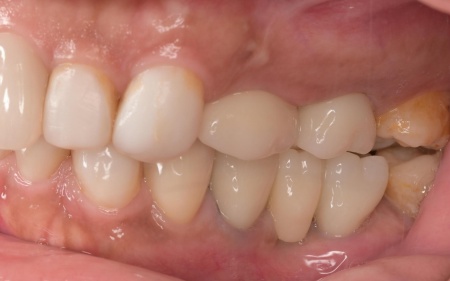

拝見したところ、もともと左上の歯と左下前歯が欠損しているうえ、奥歯の欠損も進んでいたため、噛み合わせが低くなっていました。

奥歯が噛み合わない状態になったことで、上前歯が前方に押し出され、出っ歯のようになっています。

また、下の歯は歯根だけが残る「残根」もあり、全体的に噛み合わせが不安定です。

さらに食いしばりの習慣があることから、残っている歯や顎関節に過度な負荷がかかっていると考えられます。

最初に前歯の位置と噛み合わせの高さを整えるための矯正治療を行い、その後、被せ物による治療で噛み合わせと審美性を回復する方法を提案しました。

上顎の前歯2本ずつと奥歯4本(左右中切歯・第2小臼歯・第1大臼歯)、下顎の奥歯7本(左第1小臼歯・左右第2小臼歯・第1大臼歯・第2大臼歯)には、見た目が自然なセラミックの被せ物「ジルコニアクラウン」を装着しました。

ジルコニアは、金属を使わないため金属アレルギーの心配が少ない点、人工ダイヤモンドと呼ばれるほどの強度をもち噛む力の強い奥歯にも適している点がメリットです。